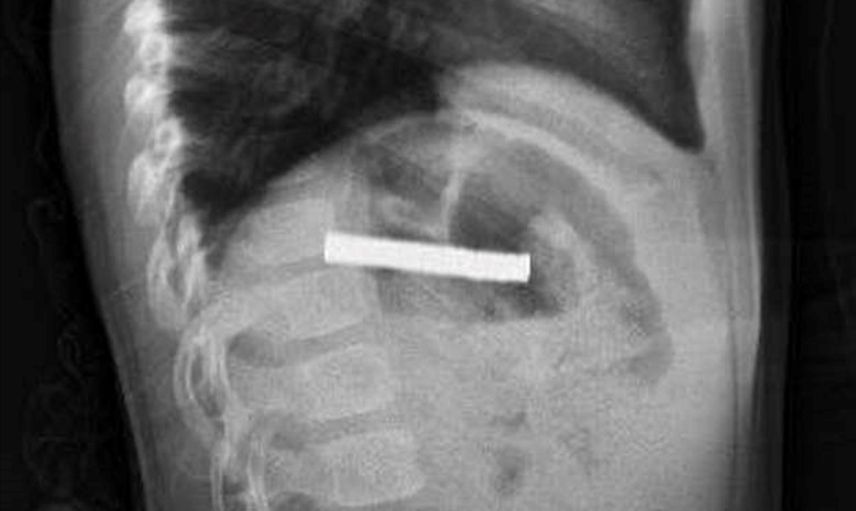

Erzurum'da evde oyun oynarken bulduğu 19 mıknatısı yutan 3 yaşındaki çocuk, rahatsızlanması üzerine ambulansla Erzurum Şehir Hastanesi'ne kaldırıldı. Yapılan tetkiklerin ardından hasta, acil durum nedeniyle ambulans helikopter ile Fırat Üniversitesi (FÜ) Hastanesi'ne sevk edildi.

FÜ Çocuk Gastroenteroloji Hepatoloji ve Beslenme Bilim Dalı Başkanı Prof. Dr. Yaşar Doğan ve ekibinin tetkiklerinde mıknatısların birbirine yapışarak çocuğun yemek borusunu tıkadığı tespit edildi. Müdahale sırasında mıknatıslar yemek borusundan mideye alınarak, mideden özel bir file ile çıkarıldı. İşlem başarılı geçti.

Elazığ'da 3 yaşındaki çocuğun yuttuğu ve yemek borusunu tıkayan 19 mıknatıs, Fırat Üniversitesi Hastanesi'nde yapılan başarılı bir operasyonla çıkarıldı.